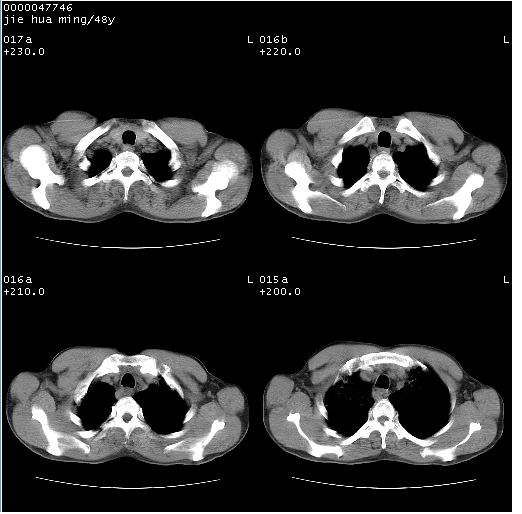

以下是引用dr.yang在2008-5-1 6:25:00的发言:[br]两肺广泛毛玻璃样的片状影,密度不均,边缘欠清,呈碎石路样改变,[br]考虑,1双肺间质性肺炎,2肺泡蛋白沉积症3支气管肺泡癌[br]

以下是引用hhcckk在2008-5-1 8:06:00的发言:[br]支持肺泡蛋白沉积症[br]依据:[br]1、病灶边缘清楚----地图征[br]2、病灶内部小叶间隔或小叶内间隔增厚所形成的网格状影----碎石路样表现[br]3、抗炎治疗无效(炎症抗炎治疗有效)[br]4、纵隔内未见肿大淋巴结(肺泡细胞癌时常有)[br][br]附肺泡蛋白沉积症资料[br][br]肺泡蛋白沉积症(pulmonary alveolar proteinosis)是一种原因不明的以肺泡腔内大量含脂糖蛋白样物质沉积为特征的疾病。[br]病理改变:(1)肺泡和细支气管腔内充满大量含脂糖蛋白样的粘稠物质,该物质为颗粒状或絮状的糖原pas染色阳性的磷脂蛋白。(2)肺泡壁及其间隔无异常改变。胸膜和淋巴结不受累及。(3)晚期可出现弥漫性肺间质纤维化。[br]临床表现:(1)好发年龄30~50岁,男性多于女性,偶见于儿童;(2)主要症状为呼吸困难、咳嗽、低热、消瘦、低氧血症和杵状指等。1/3的患者无症状。(3)实验室检查:痰液或肺泡灌洗液中可找到pas染色阳性颗粒物质。[br]hrct表现:肺泡蛋白沉积症具有特征性改变,即“碎石路样”表现(crazy-paving appearance,cpa)。主要包括(1)斑片状磨玻璃影:指肺野密度朦胧增加,内可见肺血管纹理影,系肺泡腔内充满低密度的磷脂蛋白物质所致。(2)其内部小叶间隔或小叶内间隔增厚所形成的网格状影,为小叶间隔水肿、肺泡壁内淋巴细胞和巨噬细胞浸润以及小叶内淋巴管扩张的缘故。(3)病灶边缘清楚,呈地图样分布于肺野外围或肺门及中央区。[br]

以下是引用zsl6918在2008-5-1 7:35:00的发言:[br]双肺磨玻璃样病变,可见铺碎路石征,病变区与正常区交错。边界清晰。符合肺泡蛋白质沉着征,高分辨扫描会更清楚漂亮。建议临床肺泡灌洗。

以下是引用yangyudong333在2008-5-1 5:36:00的发言:[br][br] 两肺广泛毛玻璃样的片状影,密度不均,边缘欠清,呈碎石路样改变,[br]考虑,1双肺间质性肺炎,2肺泡蛋白沉积症[br]